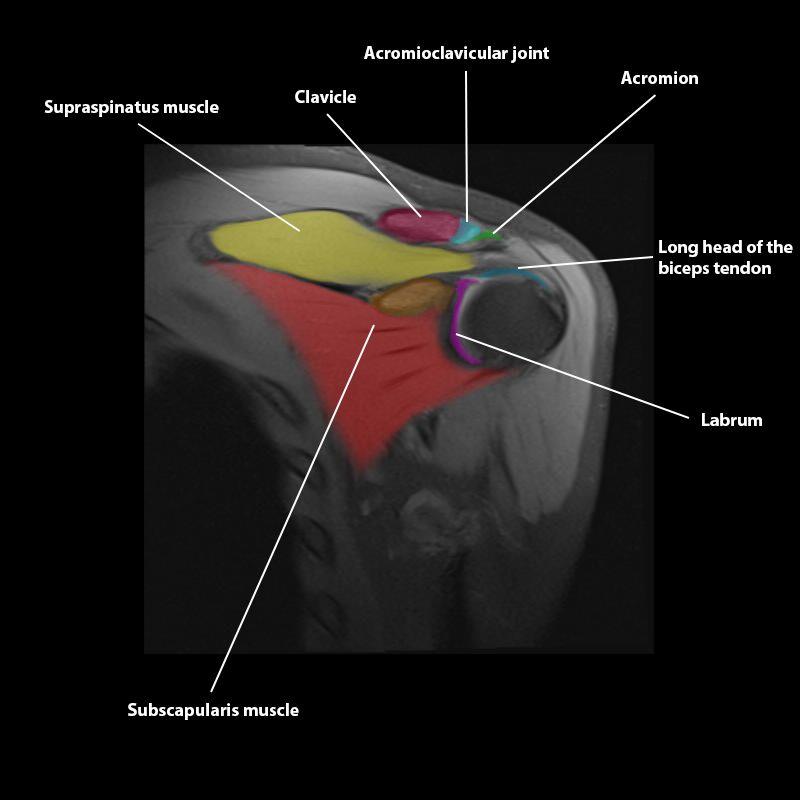

Shoulder MRI Anatomy